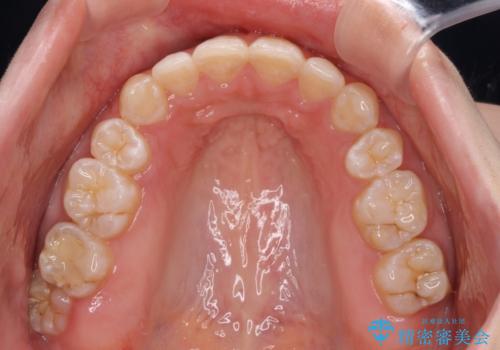

前に出ている上顎 抜歯矯正で唇を閉じやすく

第二小臼歯抜歯はイレギュラーな治療手段であり、治療期間が延びる傾向にありますが、舌のトレーニングをしっかりと行ってくださり、2年弱という非常に短い期間で理想的な仕上がりを達成することができました。